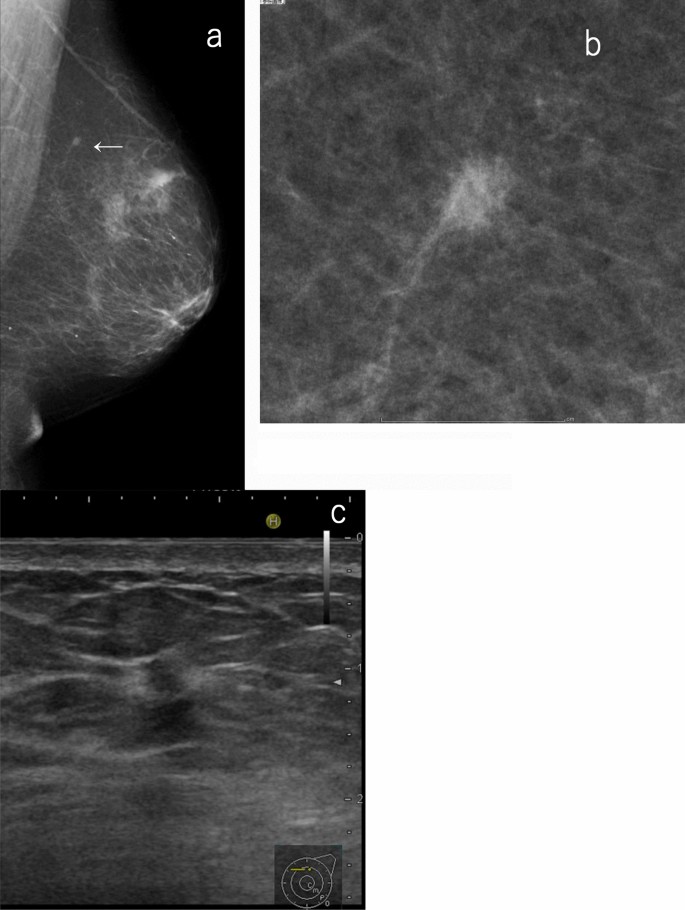

It should be noted that a mass in the deep or the peripheral part of the large breast may not be easily detected by ultrasound. Further, a small invasive tumor existing in adipose tissue may not be easily detected by ultrasound even if it can be confirmed by mammography, especially when performing ultrasound without the findings and assessment of the corresponding mammography (separate mammography/ultrasound combined method). If there is a possibility (as described above), the mammography findings should be prioritized even if there are no abnormalities on ultrasound (Fig. 3). When ultrasound is performed based on the findings and assessment of the corresponding mammography (simultaneous mammography/ultrasound combined method), it is possible to perform targeted scanning on lesion candidates so that the ultrasound can be efficiently performed. In this sense, its reliability is enhanced.

A case of a small, indistinct mass on mammography but no abnormal findings on ultrasound. a, b Mammography: small indistinct mass (allow), SMC. Screening ultrasound: no abnormality, SUC 1. The overall assessment category: SC 4. c Targeted ultrasound: indistinct mass with interruption of the anterior border of the mammary gland and halo sign (4 mm), DUC4. Histopathology: invasive ductal carcinoma. This case is difficult to detect based on screening ultrasound, especially when performing ultrasound without reference to mammography findings (separate mammography/ultrasound method) (SMC screening mammography category, SUC screening ultrasound category, SC screening category, DUC diagnostic ultrasound category)